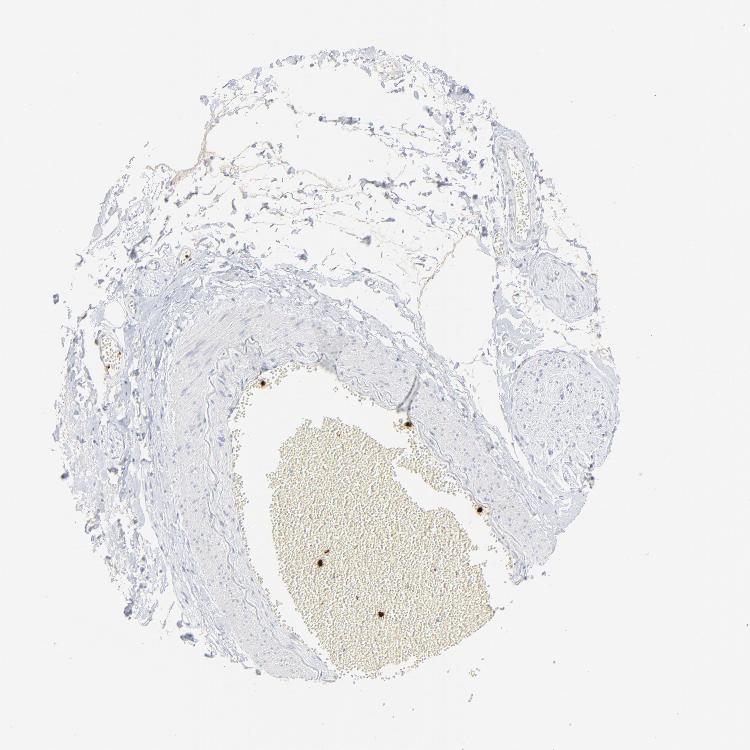

SOFT TISSUE 1 - Antibody stainingi

Antibody staining in the annotated cell types in the current human tissue is reported as not detected, low, medium, or high, based on conventional immunohistochemistry profiling in selected tissues. This score is based on the combination of the staining intensity and fraction of stained cells.

Each image is clickable and will lead to virtual microscopy that enables deeper exploration of all samples and also displays staining intensity scores, fraction scores and subcellular localization as well as patient and tissue information for each sample.

Antibody HPA002695Antibody CAB016549Antibody CAB016550

Chondrocytes Not detected--

Fibroblasts Not detectedNot detectedNot detected

Peripheral nerve Not detectedNot detectedNot detected